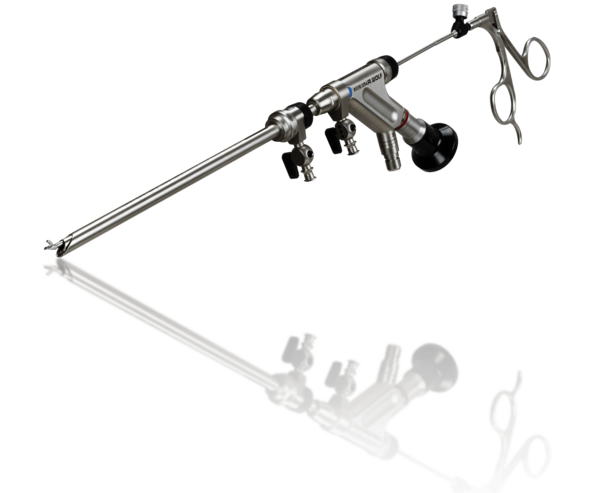

- Hochauflösende Diskoskope mit Arbeitslänge für posterolateralen und lateralen transforaminalen Zugang.

- Optimiertes Verhältnis von großem Arbeitskanal zu Außendurchmesser für minimalinvasiven Zugang und effektive Operation.

- Optimiertes Flüssigkeitsmanagement durch ausgeklügelte Dimensionierung des Zu- und Abflusses - Vermeidung von Nervenkompression durch hohe Drücke der Spülflüssigkeit.

- Arbeitshülsen mit atraumatischem distalem Design zum Schutz der neuralen Strukturen.

- Stabile Faßzangen und Stanzen für effektive Weichteil- und Knochenresektion mit Überlastungsschutz.

- Endoskopisches Hochgeschwindigkeits-Bohrsystem mit wiederverwendbaren und Einwegwerkzeugen für die mechanische Knochen- und Weichteilresektion.

- Tipcontrol-Instrumente für die 4-MHz-Radiofrequenzkoagulation und -ablation.